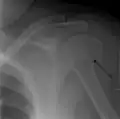

Proximal

Definitive diagnosis of humerus fractures is typically made through radiographic imaging. For proximal fractures, X-rays can be taken from a scapular anteroposterior (AP) view, which takes an image of the front of the shoulder region from an angle, a scapular Y view, which takes an image of the back of the shoulder region from an angle, and an axillar lateral view, which has the patient lie on his or her back, lift the bottom half of the arm up to the side, and have an image taken of the axilla region underneath the shoulder.[9] Fractures of the humerus shaft are usually correctly identified with radiographic images taken from the AP and lateral viewpoints.[12] Damage to the radial nerve from a shaft fracture can be identified by an inability to bend the hand backwards or by decreased sensation in the back of the hand.[5] Images of the distal region are often of poor quality due to the patient being unable to extend the elbow because of pain. If a severe distal fracture is suspected, then a computed tomography (CT) scan can provide greater detail of the fracture. Nondisplaced distal fractures may not be directly visible; they may only be visible due to fat being displaced because of internal bleeding in the elbow.[7]

Humerus fractures are among the most common of fractures. Proximal fractures make up 5% of all fractures and 25% of humerus fractures,[9] middle fractures about 60% of humerus fractures (12% of all fractures),[12] and distal fractures the remainder. Among proximal fractures, 80% are one-part, 10% are two-part, and the remaining 10% are three- and four-part.[22] The most common location of proximal fractures is at the surgical neck of the humerus.[3] Incidence of proximal fractures increases with age, with about 75% of cases occurring among people over the age of 60.[11] In this age group, about three times as many women as men experience a proximal fracture.[23] Middle fractures are also common among the elderly, but they frequently occur among physically active young adult men who experience physical trauma to the humerus.[12] Distal fractures are rare among adults, occurring primarily in children who experience physical trauma to the elbow region.[7]